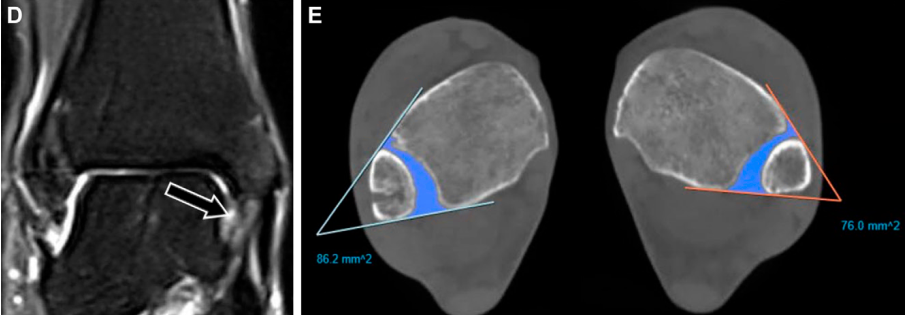

不稳定性损伤的MRI诊断要点

尽管MRI能精准评估韧带和骨性损伤,但无法对远端胫腓联合进行动态评估。因此,MRI可显示解剖学损伤,但不能直接确诊关节不稳,仅能通过间接影像学表现推断。MRI上提示胫腓联合不稳的关键征象包括:后下胫腓韧带完全撕裂、后踝骨折、三角韧带完全撕裂及胫腓联合近侧腓骨骨折。

下胫腓后韧带完全断裂是判断胫腓联合不稳的可靠指标,其敏感性为74%,特异性为 78%,阳性预测值为54%。后踝骨折对关节生物力学的影响与下胫腓后韧带完全断裂相当,且单独发生的概率极低,仅占所有踝关节骨折的1%~4%:

但该骨折常合并更复杂的损伤,包括双踝骨折、三踝骨折和腓骨近端骨折。约82%的Maisonneuve骨折患者会出现后踝骨折的症状和体征。尽管单纯三角韧带损伤通常为稳定性损伤,但当其与远端胫腓联合损伤并存时,会导致踝关节冠状面明显不稳。

下胫腓联合损伤常合并其他结构异常,MRI可清晰显示这些病变。距腓前韧带损伤最为常见,发生率约64%,且与胫腓联合分离密切相关,尤其在踝关节内翻加跖屈损伤中更易出现;骨挫伤发生率约25%,在急性损伤中更为常见,且多位于内侧,与内翻所致的挤压和牵张力相关。

距骨穹窿骨软骨损伤的发生率约28%,在急、慢性损伤中发生率相近;约33%的慢性损伤病例会出现胫腓关节对合不良,该表现由关节长期不稳或韧带愈合不良所致,会增加关节功能持续障碍和退变的风险。

负重位CT

负重位CT是新兴的检查技术,可反映足踝部的生理负荷状态,但早期研究中,其测量的损伤组与对照组胫腓联合的差异结果存在矛盾。

骨分割技术的发展使更特异、详细的测量指标得以应用,可通过获取面积和体积参数,对比患者患侧与健侧的胫腓关节,且初步结果良好。例如,研究显示,负重状态下,不稳定关节的胫腓联合面积较健侧增加13.7%(患侧比健侧高22.9mm²),而稳定关节的面积仅增加3.1%。在胫骨关节面近侧5cm 范围内均可测量关节体积,以体积大于11.6cm³为阈值,诊断胫腓联合不稳的敏感性为95%、特异性为83%、准确性为 90%。

近期出现的半自动和自动骨分割技术,结合距离和覆盖度成像技术,可提供更客观、可量化的检测数据,有望发现以往未被识别的损伤相关异常。